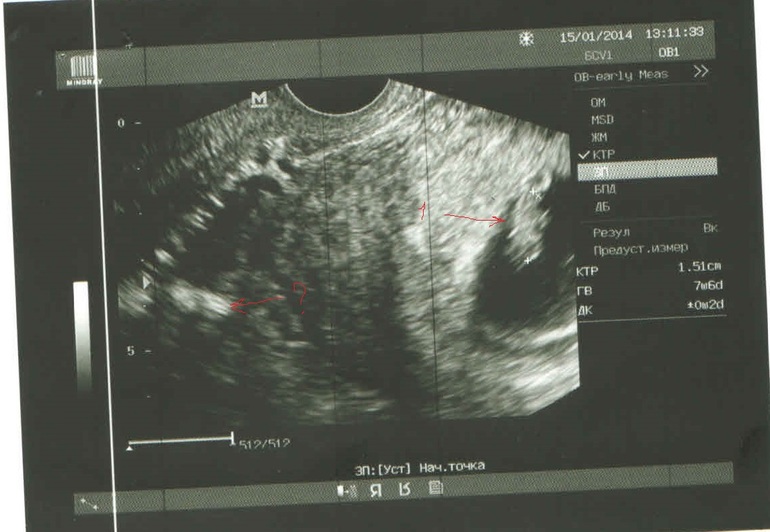

Перед тем, как встать на учет ко врачу, я сделала узи. Нашли 1 плодное яйцо, у эмбриончика СБ просматривалось. Срок 8 недель.

Участковый врач после осмотра на кресле сказала, что матка больше срока и скорее всего у меня там не один.

В ближайшие дни нет возможности посетить узиста - нахожусь в командировке, а муж на снимке "разглядел" еще одного.

Посмотрите, если не трудно, и напишите свое мнение.

Если второй и есть - то где-то возле первого, но точно не там где вы поставили "?"